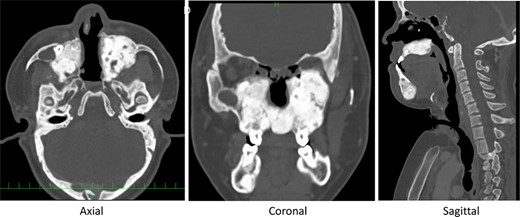

Post-operative CT midline bone has been drilled out, and space for nasal airflow has been widened.